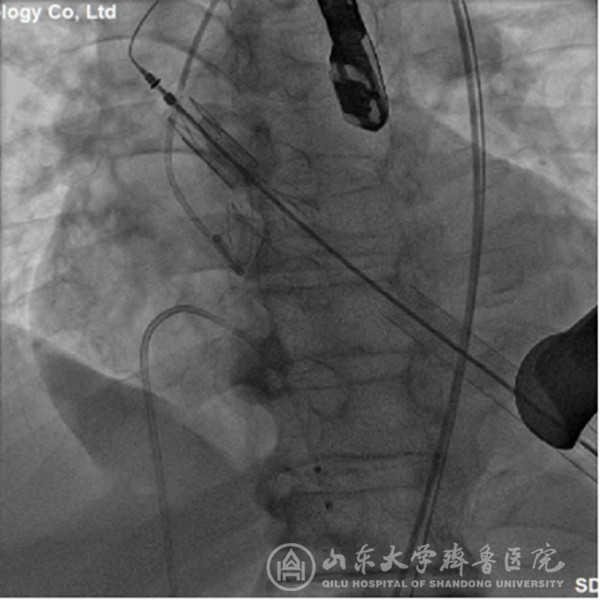

经过充分细致地准备,TAVI团队在复合手术室实施手术。根据患者的病情特点,术中做好各种应急预案,备好体外循环,维持血流动力学平稳。根据术前CT分析和术中主动脉根部造影情况(图1),选择最佳投照体位。选用29mm的介入主动脉瓣膜,经心尖途径,依次定位、顺序释放介入瓣膜(图2),造影及心脏超声检查示:人工瓣膜启闭功能正常,主动脉瓣无返流,未见明显瓣周分流(图3)。因患者心功能极差,手术操作过程中,多次出现频发及多源性室早、血压下降等情况,TAVI团队(心外科、心内科、麻醉科、手术室、心脏超声室等)医护人员齐心协力、整体配合,精心操作,积极对症处理,用时近2小时顺利完成手术。患者术后出现左心衰、血压低、尿量少等情况,给予积极处理,病情逐渐稳定。术后第2天拔气管插管,术后第5天转出监护病房。术后第7天,可下床活动,无心慌、胸闷等症状。术后第12天,病情稳定,治愈出院。术后2个月随访,患者基本日常活动不受影响,饮食正常,无心衰症状,恢复效果满意。

图2 在透视下,依次释放介入瓣膜系统的定位键及瓣膜